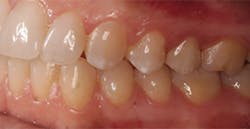

The next day, a good case opportunity presented itself. I had to prepare and scan No. 13 for a crown. I figured it was anteriorly positioned enough that I could test the esthetics, but it was posterior enough that the stakes weren’t too high. Nevertheless, you can see from Figures 1a–1c that we were thrilled with the results. Additional restoration examples can be seen in Figures 2 and 3.

Figures 1a–1c:

1a: Prepared No. 13, 1b: True Definition scan merged with clinical photo, 1c: No. 13 with Lava Esthetic full contour zirconia crown

Figures 2 and 3: Additional restorations using Lava Esthetic